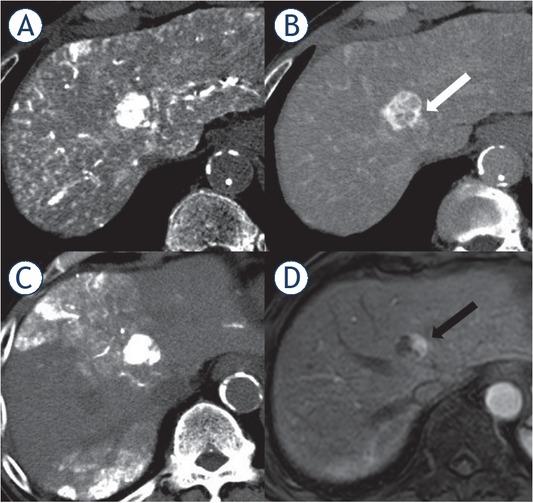

Figure 1